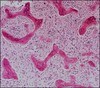

What kind of cartilaginous tumor is this?

Chondroma

- Nodules of mature cartilage within a fatty bone marrow

- Low cellularity, lack of pleomorphism (just mature cartilage)